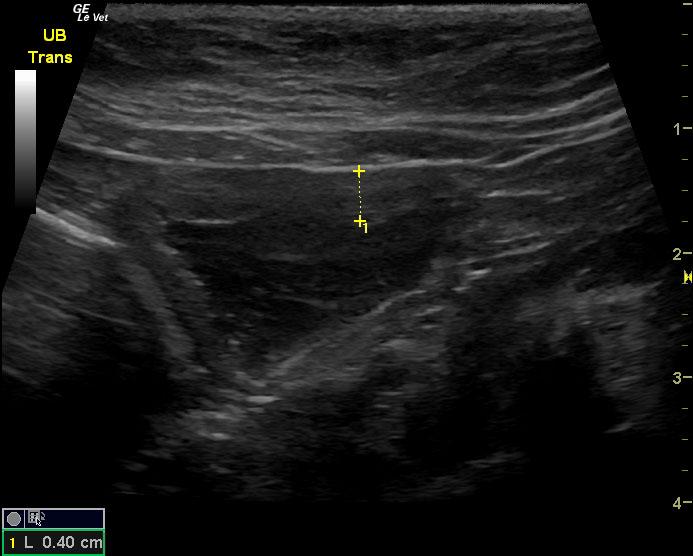

A 6-year-old SF DSH cat was presented for evaluation of chronic cystitis that was non-responsive to antibiotic and Adequan therapy. Both urinalysis and urine culture were within normal limits.

A 6-year-old SF DSH cat was presented for evaluation of chronic cystitis that was non-responsive to antibiotic and Adequan therapy. Both urinalysis and urine culture were within normal limits.